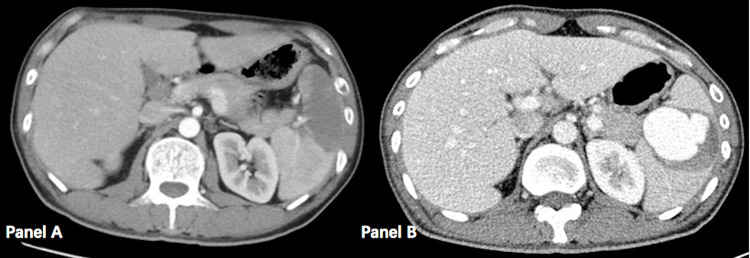

感染性心内膜炎是一种严重的感染性疾病,除了瓣膜损伤引起的心力衰竭和心律失常等心脏并发症外,还可能导致化脓症栓塞、转移性脓肿和真菌性动脉瘤等心外并发症。在此,我们报告一例罕见的由感染性心内膜炎引起的脾梗死,术后三周经CTA和DSA证实为脾动脉瘤。动脉瘤动脉栓塞后,患者最终完全康复。

Infective endocarditis is a severe infectious disease that, in addition to cardiac complications such as heart failure and arrhythmias caused by valve damage, may also lead to extracardiac complications such as septic embolization, metastatic abscesses, and mycotic aneurysms. Here, we report a rare case of splenic infarction resulting from infective endocarditis, subsequently leading to the development of a splenic artery aneurysm three weeks post-surgery confirmed both by CTA and DSA. Following arterial embolization of the aneurysm, the patient eventually recovered completely.